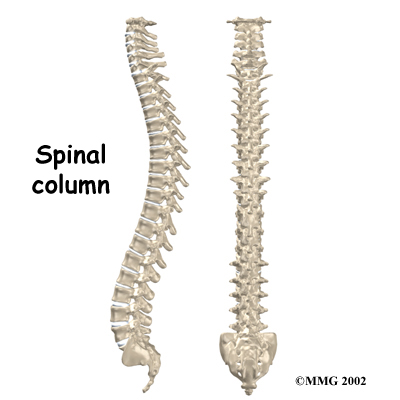

The human spine is made up of 24 spinal bones, called vertebrae. Vertebrae are stacked on top of one another to create the . The spinal column gives the body its form. It is the body's main upright support.

The back portion of the spinal column forms a . When the vertebrae are stacked on top of each other, these bony rings create a hollow tube. This bony tube, called the spinal canal, surrounds the as it passes through the spine. Just as the skull protects the brain, the bones of the spinal column protect the spinal cord.